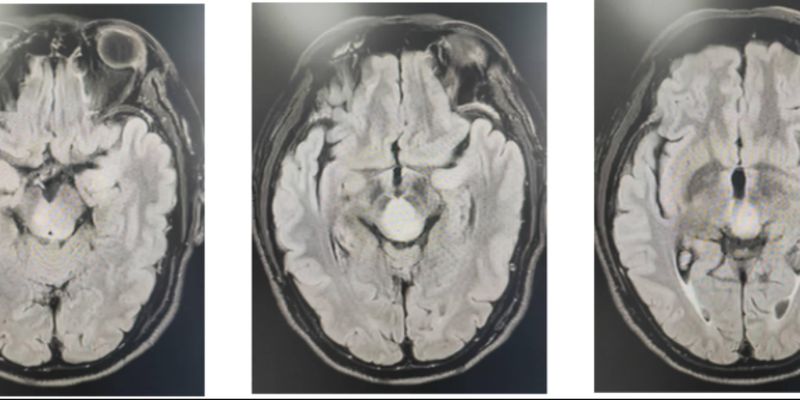

图:靶区范围的定义与划分

- 实验组: 采用创新的HSIB-IMRT(中等分割同步增剂量调强放疗)方案。研究人员利用多模态MRI和弥散张量成像(DTI)技术,精准识别肿瘤的浸润路径,从而制定个体化的、更小的放疗靶区(CTV)。

传统的放疗靶区勾画通常在手术切除区域及水肿区外延约2厘米,这种“一刀切”的方式忽略了胶质瘤倾向于沿脑白质纤维束浸润的生物学特性,使得大量健康的脑组织被纳入照射范围。因此,如何在保证疗效的同时,更精准地定义放疗靶区,减少对正常大脑的损伤,成为高危胶质瘤治疗领域亟待解决的关键问题。

- 显著缩小的放疗靶区: 实验组的放疗靶区体积(CTV)中位数显著小于对照组(174.4 cm³ vs 225.0 cm³),靶区体积成功缩减了约22.5%。这意味着实验组患者有更多的正常脑组织免受了不必要的放射损伤。